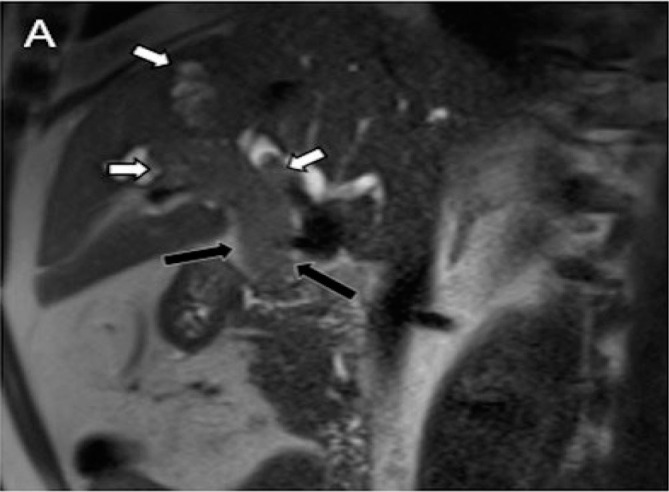

Abstract Image